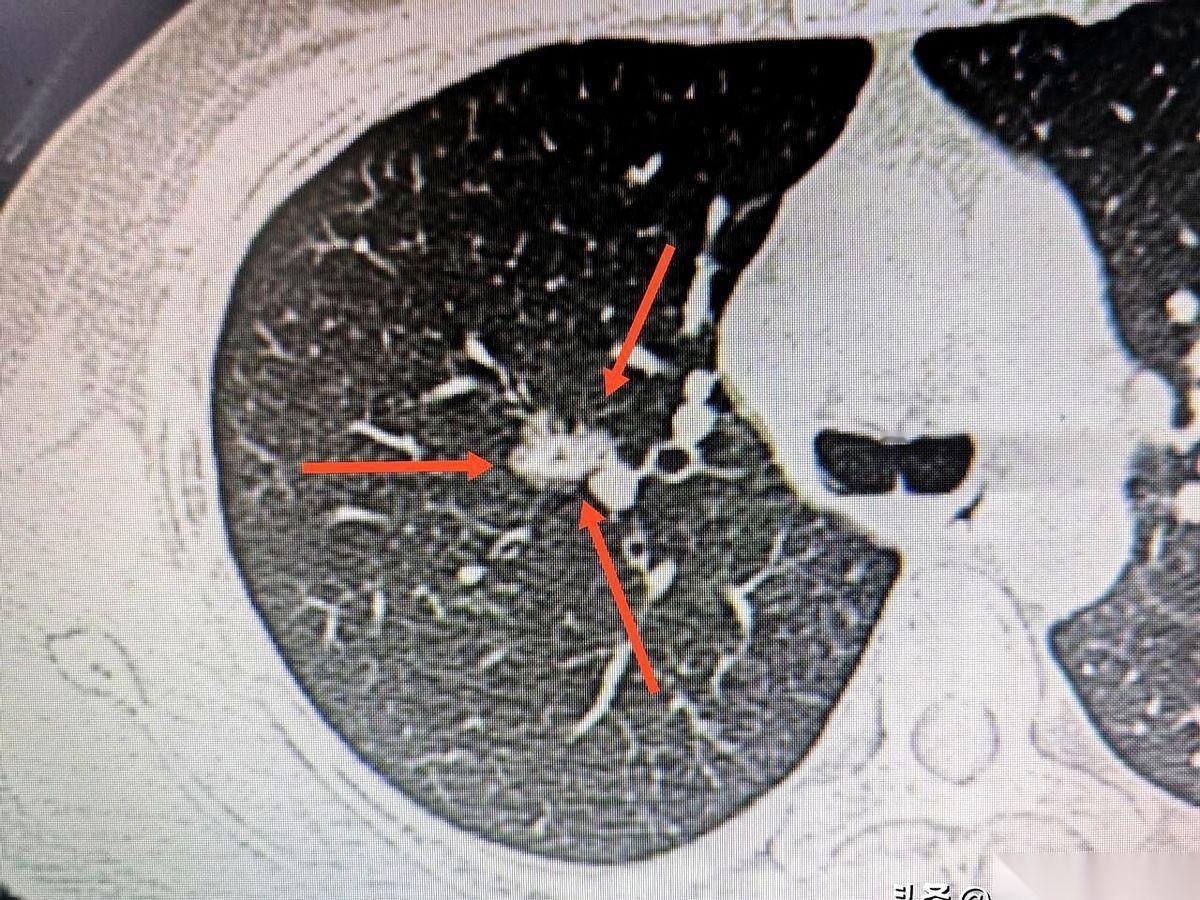

900多公里。 从山东德州,到杭州。 当术中病理结果——“浸润性腺癌”这几个字传回手术室的时候,你能感觉到,空气都瞬间凝固了。 说真的,有时候觉得我们这些当医生的,手里拿的哪是手术刀啊,分明是别人一家子沉甸甸的希望和托付。 跨越小半个中国来找我们,这份信任,比手术刀还重。 我们能做的,就是不辜负。 把每一个细节做到极致,把创伤降到最低。看着微创手术顺利结束,心里那块大石头,才算落下一半。 是的,一半。 手术结束了,但对这个家庭来说,真正的战斗,才刚刚开始。 加油吧,素未谋面的朋友。